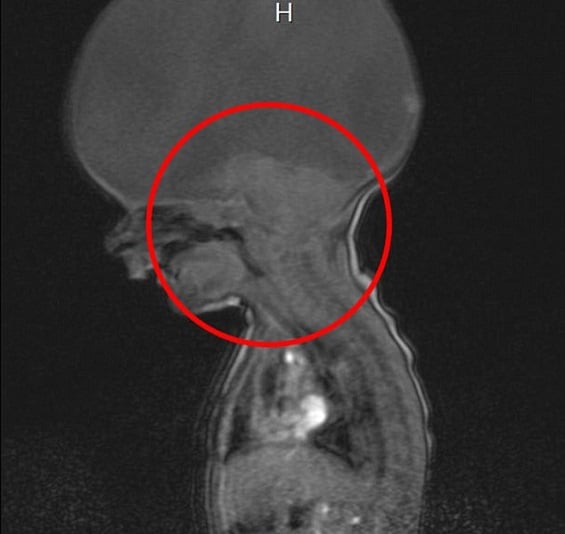

في صورة شعاعية صادمة، يظهر رأس الطفل البريطاني آرون الذي ولد قبل عامين، خالياً تماماً من الدماغ، باستثناء قسم صغير في نهاية العنق، يسمح له فقط بالحركة والتنفس.

وشخص الأطباء مرض آرون بأنه اضطراب نادر يدعى "اندماج مقدم الدماغ"، إذ ولد مع جذع الدماغ فقط، وهو ما يسمح له بالحركة والتنفس، ولكن ليس لديه دماغ كامل.